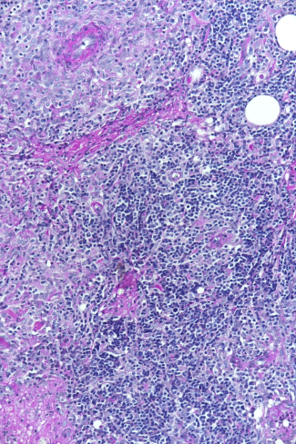

Das Krankheitsbild von Balu ist sehr unüblich. Nicht zuletzt muss selbst bei einem so jungen Hund auch an Hautkrebs gedacht werden, weshalb wir uns zur Entnahme von Gewebeproben unter einer kurzen Narkose entscheiden. Der Gewebebefund ist ebenfalls unüblich: Der Pathologe diagnostiziert einen bestimmten Typ einer entzündlichen Veränderung der Haut (Dermatitis). Eine erweiterte Gewebeuntersuchung weist nach, dass der Hund nicht an einer Leishmaniose leidet - diese parasitäre Krankheit könnte nämlich ein ähnliches Bild verursachen. Abschliessend wird also die Diagnose einer "pyogranulomatösen Dermatitis/Adnexitis" gestellt.

Beim sogenannten "sterilen pyogranulomatösen Syndrom" des Hundes handelt es sich um eine selten auftretende Entzündung der Haut, deren Ursache nicht geklärt ist. Das Immunsystem beginnt, körpereigene Strukturen anzugreifen, was zu Knoten, Haarausfall, nässenden Schwellungen und Geschwüren führen kann. Betroffene Hunde können auch systemische Zeichen wie Lethargie und Appetitverlust zeigen; die Diagnose kann nur über Gewebeproben gestellt werden. Da die Ursache des Problems unklar ist, bleibt keine andere Möglichkeit, als das Immunsystem mit Medikamenten davon abzuhalten, den Körper anzugreifen.

Wir danken Dr. Dr. U. Hetzel vom Institut für Veterinärpathologie der Uni Zürich herzlich für die mikroskopischen Aufnahmen.